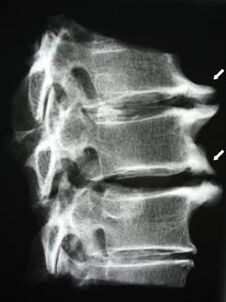

En las etapas iniciales, la osteocondrosis se detecta mediante resonancia magnética.. Posteriormente, la patología se puede diagnosticar mediante radiografía. En las radiografías de la columna cervical se nota una reducción en la distancia entre las vértebras, cambios patológicos en las articulaciones facetarias y osteofitosis.

| Osteocondrosis cervical | La aparición de cambios patológicos en uno o más segmentos de movimiento de la columna. Deterioro de la movilidad de la columna, desarrollo de síndromes de dolor miofascial y pellizco de las raíces espinales. | Dolor, parestesia y trastornos motores en la zona del cuello, que se extienden a la nuca y a las extremidades superiores. Detección de cambios característicos en la columna mediante imágenes de resonancia magnética y rayos X (osteofitos, distancia vertebral reducida, signos de daño en las articulaciones intervertebrales) |